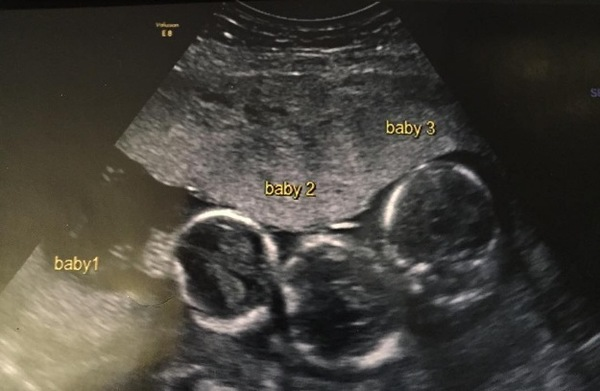

what are the odds of 200 million to one? When Becki-Jo Allen and Liam Tierney heard the amazing news two years ago, they immediately told their only daughter, Indiana. The couple, who live outside Liverpool, UK, were thinking about expanding their family, but were taken aback when Becki-Jo’s ultrasound revealed their daughter was carrying three babies instead of one or two. Becki-Jo was sick early in her pregnancy and had a lot of headaches.

The doctors arranged for her to have an ultrasound earlier than usual. That’s when they found out they were expecting triplets. That was the biggest surprise of my life! We left the office really unhappy because we don’t have triplets in the family, Becki-Jo told the Liverpool Echo.